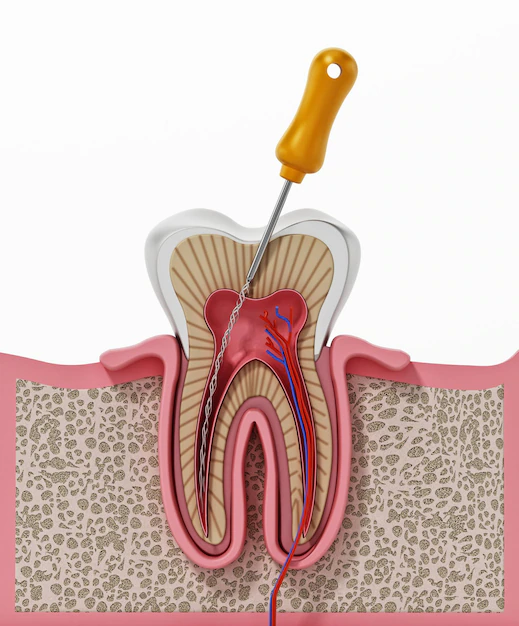

ROOT CANAL TREATMENT

Root canal treatment, also known as endodontic therapy, is a dental procedure used to treat infected or inflamed pulp inside a tooth. It involves removing the damaged pulp, cleaning and disinfecting the root canal, and then sealing it to prevent further infection. This treatment helps save a tooth that might otherwise require extraction.

I am Dr. Ravi Shekar and I am thrilled to be your partner in achieving a healthy and beautiful smile. With a passion for dentistry and a focus on specialized treatments, I am dedicated to providing you with the highest quality care using state-of-the-art technology and innovative techniques. As a specialist in Root Canal procedures, I understand the importance of preserving your natural teeth.

ROOT CANALS

ROOT CANAL TREATMENT